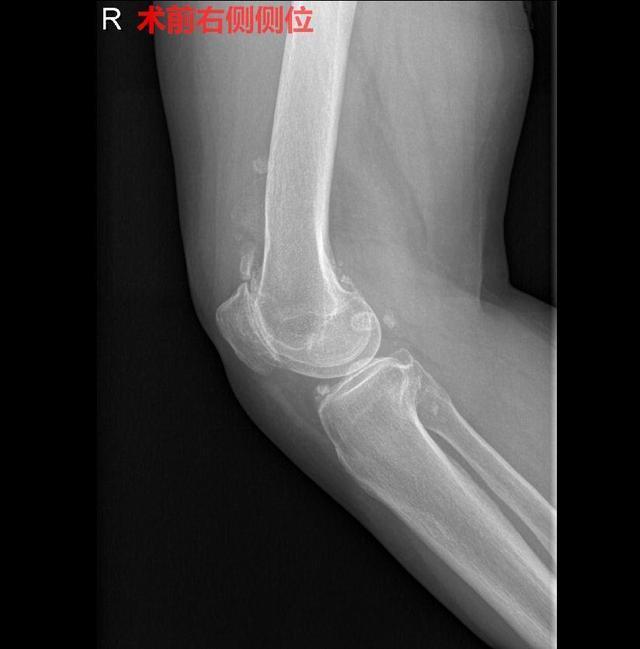

20年前,患者偶感右膝疼痛,无交锁及肿胀。15年前因疼痛加重于当地医院就诊,予止痛治疗,之后断断续续,但一直没有进行大的治疗。前几个月,患者因右膝疼痛及交锁情况逐渐加重,于是来我院就诊。入院诊断:1.右膝关节疼痛交锁查因;2.右膝关节骨性关节炎;3.膝关节游离体(右);4.左腘窝肿物性质待查;5.颈椎病。